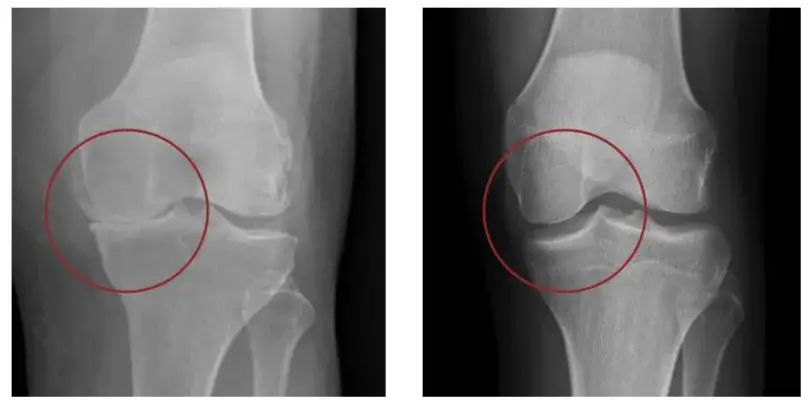

Illustration comparing healthy knee joint to one with osteoarthritis

Osteoarthritic Knee Healthy Knee